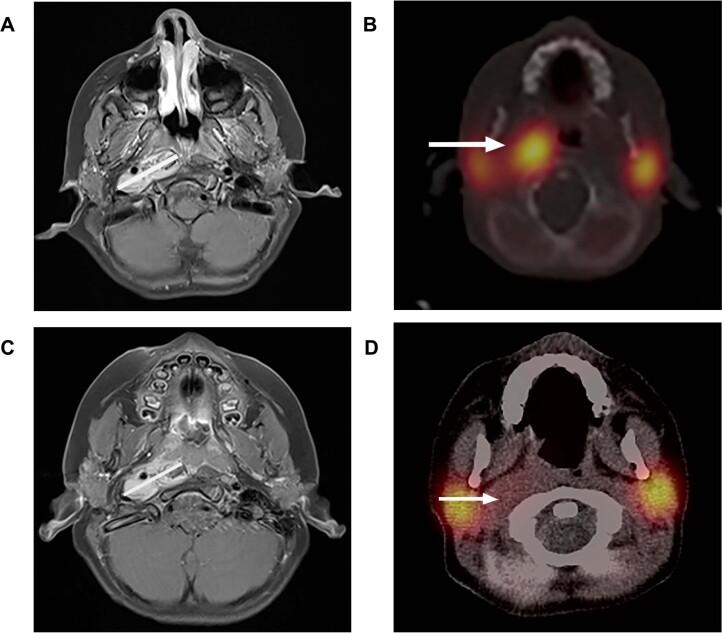

Neuroblastomas harbor ALK aberrations clinically resistant to crizotinib yet sensitive pre-clinically to the third-generation ALK inhibitor lorlatinib. We conducted a first-in-child study evaluating lorlatinib with and without chemotherapy in children and adults with relapsed or refractory ALK-driven neuroblastoma. The trial is ongoing, and we report here on three cohorts that have met pre-specified primary endpoints: lorlatinib as a single agent in children (12 months to <18 years); lorlatinib as a single agent in adults (≥18 years); and lorlatinib in combination with topotecan/cyclophosphamide in children (<18 years). Primary endpoints were safety, pharmacokinetics and recommended phase 2 dose (RP2D). Secondary endpoints were response rate and I-metaiodobenzylguanidine (MIBG) response. Lorlatinib was evaluated at 45-115 mg/m/dose in children and 100-150 mg in adults. Common adverse events (AEs) were hypertriglyceridemia (90%), hypercholesterolemia (79%) and weight gain (87%). Neurobehavioral AEs occurred mainly in adults and resolved with dose hold/reduction. The RP2D of lorlatinib with and without chemotherapy in children was 115 mg/m. The single-agent adult RP2D was 150 mg. The single-agent response rate (complete/partial/minor) for <18 years was 30%; for ≥18 years, 67%; and for chemotherapy combination in <18 years, 63%; and 13 of 27 (48%) responders achieved MIBG complete responses, supporting lorlatinib's rapid translation into active phase 3 trials for patients with newly diagnosed high-risk, ALK-driven neuroblastoma. ClinicalTrials.gov registration: NCT03107988 .

神经母细胞瘤携带 ALK 异常,临床上对克唑替尼耐药,但临床前对第三代 ALK 抑制剂洛拉替尼敏感。我们进行了一项首次在儿童中进行的研究,评估洛拉替尼联合或不联合化疗在复发或难治性 ALK 驱动的神经母细胞瘤的儿童和成人中的疗效。该试验正在进行中,我们在此报告三个已达到预先指定的主要终点的队列:儿童(12 个月至<18 岁)中洛拉替尼单药治疗;成人(≥18 岁)中洛拉替尼单药治疗;以及儿童(<18 岁)中洛拉替尼联合拓扑替康/环磷酰胺治疗。主要终点是安全性、药代动力学和推荐的 2 期剂量(RP2D)。次要终点是缓解率和 I-间碘苄胍(MIBG)反应。洛拉替尼在儿童中的剂量为 45-115mg/m/剂量,在成人中为 100-150mg。常见的不良事件(AE)是高甘油三酯血症(90%)、高胆固醇血症(79%)和体重增加(87%)。神经行为 AE 主要发生在成人中,并通过剂量暂停/减少来解决。儿童中洛拉替尼联合或不联合化疗的 RP2D 为 115mg/m。成人单药 RP2D 为 150mg。<18 岁的单药缓解率(完全/部分/轻微)为 30%;≥18 岁的缓解率为 67%;<18 岁的化疗联合缓解率为 63%;27 例应答者中有 13 例(48%)达到 MIBG 完全缓解,支持洛拉替尼迅速转化为新诊断的高危、ALK 驱动的神经母细胞瘤患者的积极 3 期试验。临床试验注册:NCT03107988。